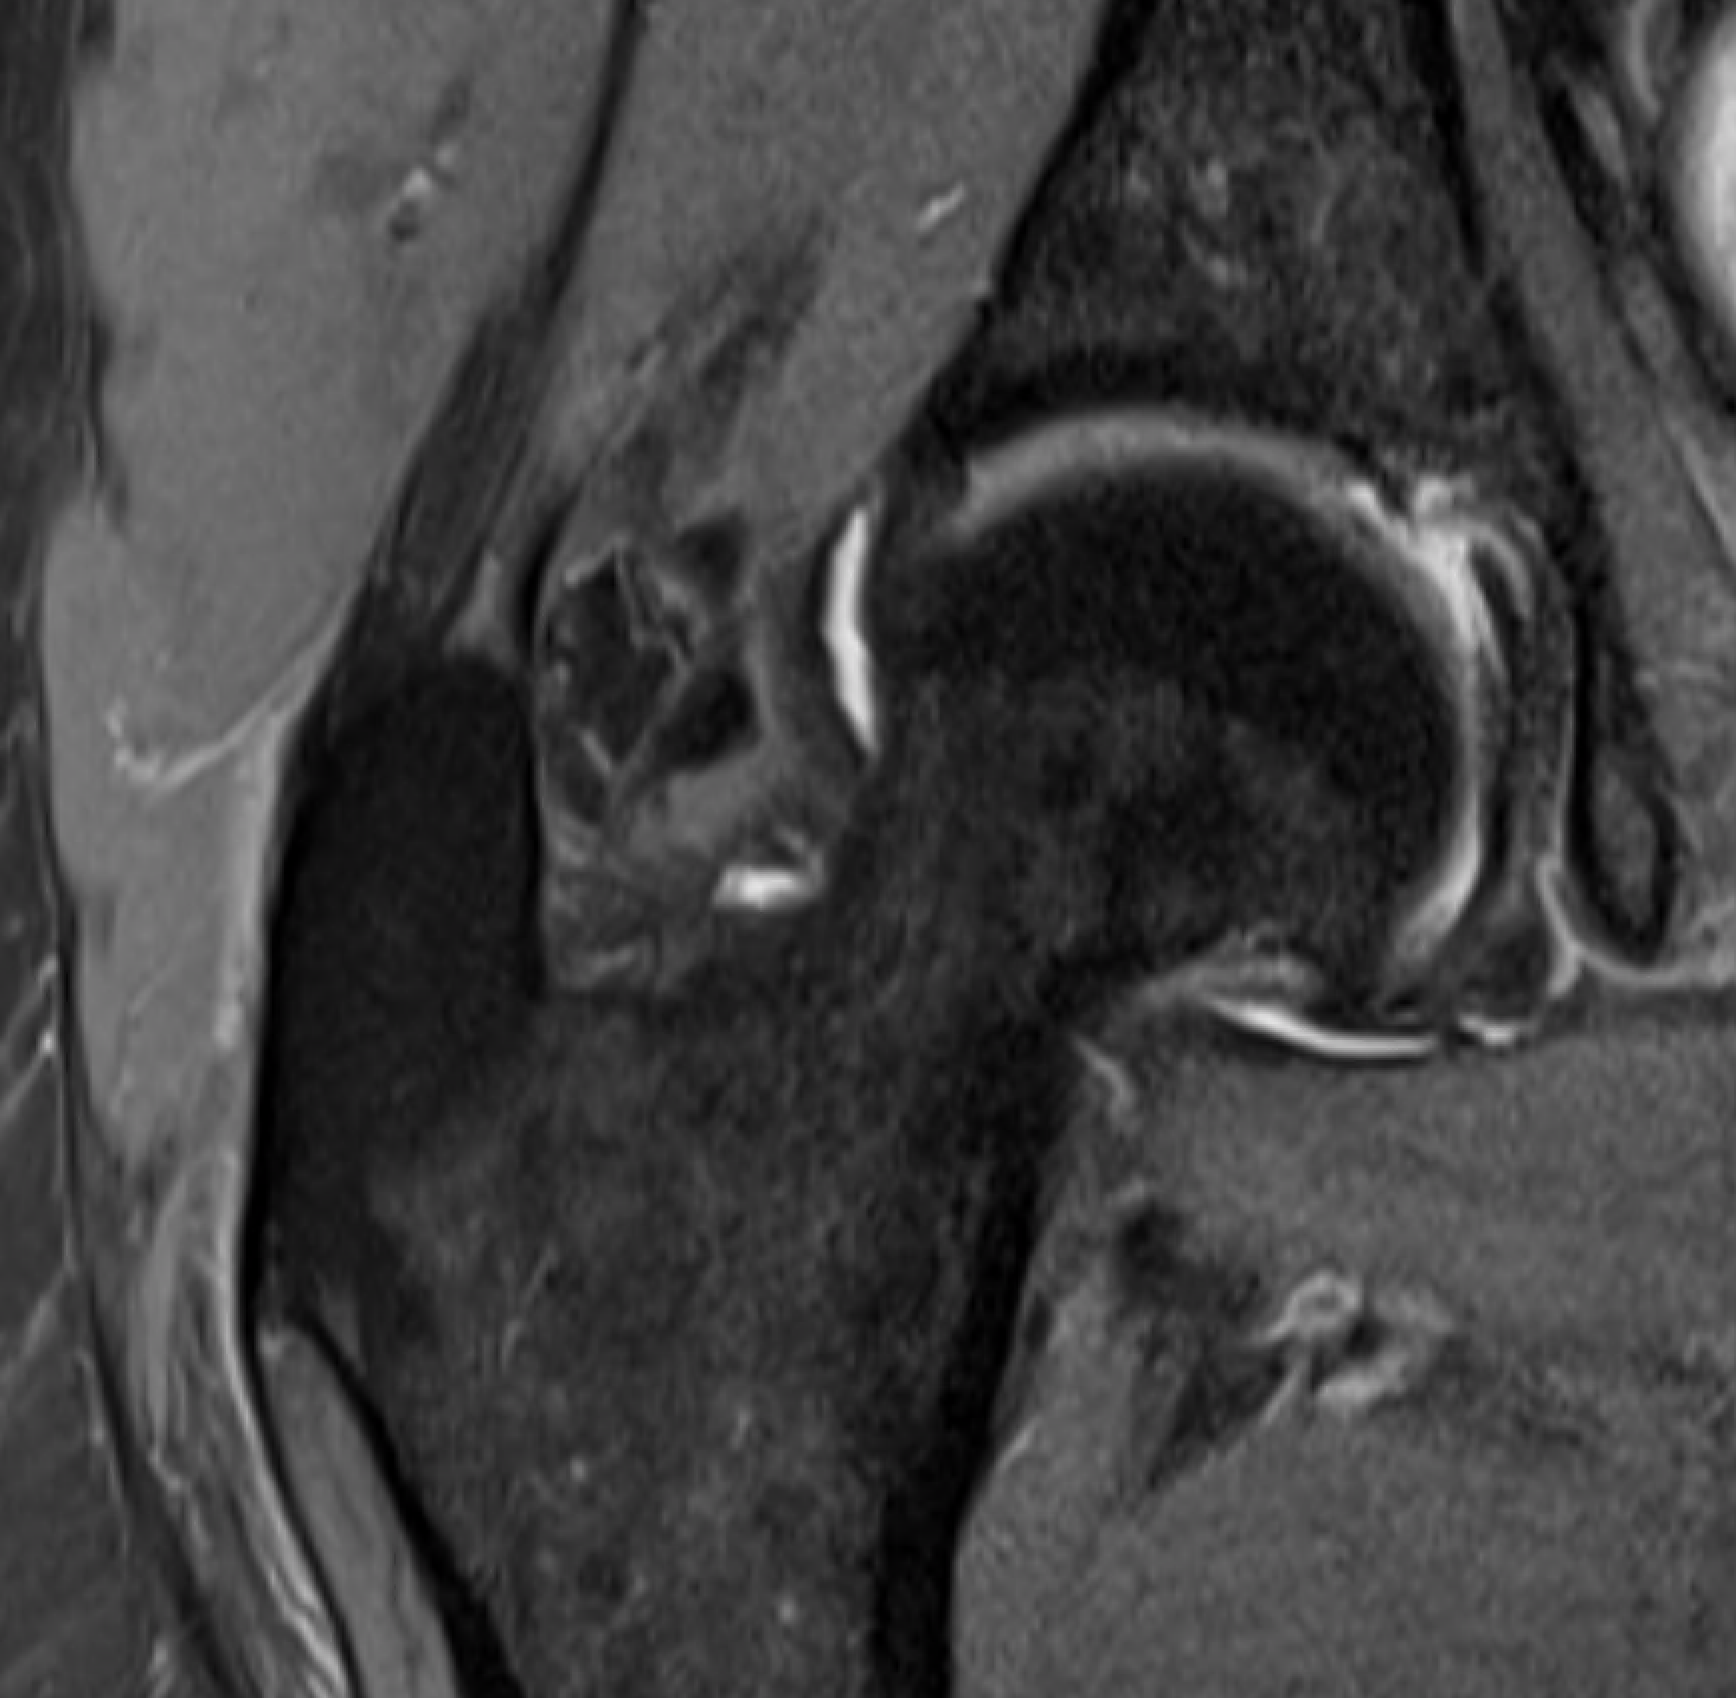

MRI

Torn gluteus medius and minimus